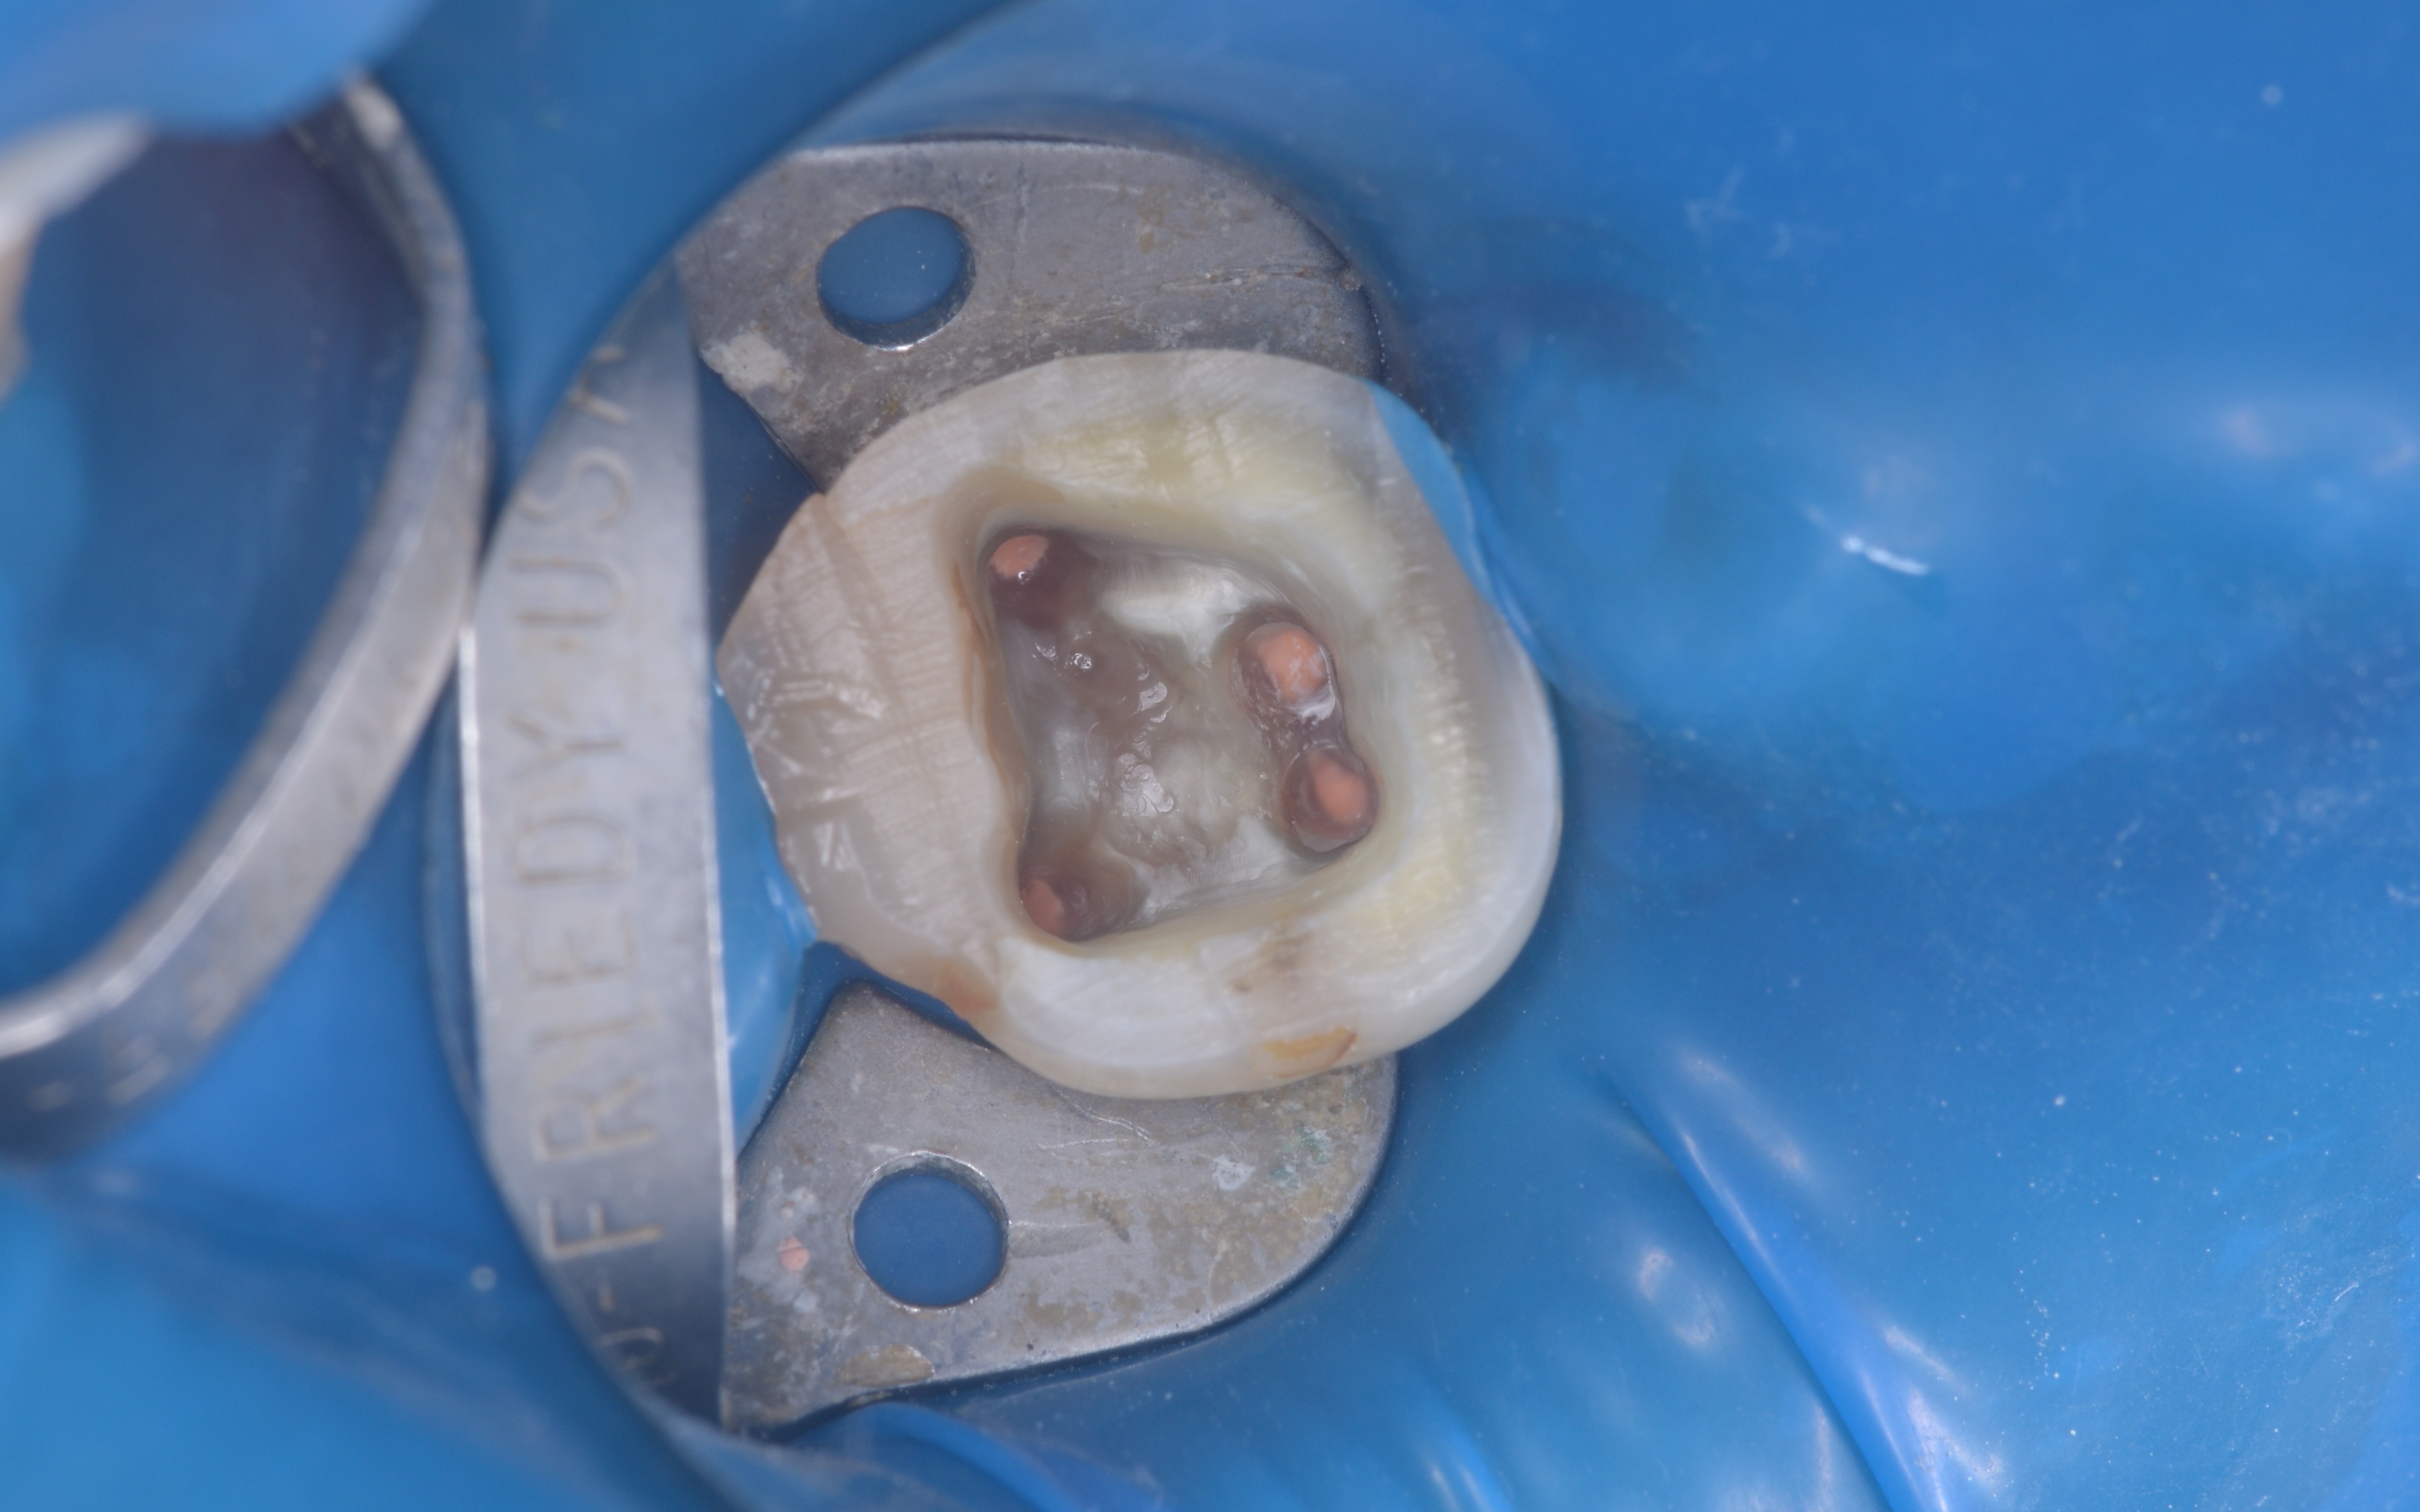

手術後は、歯茎と骨の状態が安定するまで経過観察を行い、十分に治癒したことが確認できたあと、顕微鏡を使用した「精密根管治療」を実施します。

精密根管治療とは、歯の神経が通っている根管という細い管の中を、顕微鏡で拡大しながら丁寧に清掃と消毒をする方法です。自費診療なのでやや費用がかかるものの、保険診療内の治療よりも精密で確実な処置が行えます。

感染源を丁寧に除去したあとは根管内を消毒し、薬剤でしっかりと封鎖しました。

精密根管治療を行いました。